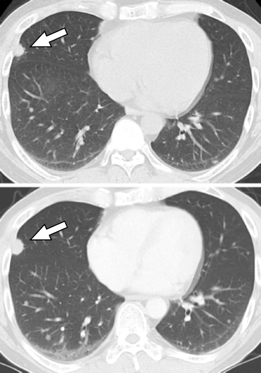

图8 36天与5个月后复查CT,示右中叶结节直径增大(箭头所示)。

因右肺中叶结节进行性增大,为进一步明确诊断,予胸腔镜肺活检,病理示结节外层有紧密的胶原纤维,中央大量凝固性坏死(图9)。

病理特染找真菌及结核菌均(-),组织标本结核菌培养及结核菌PCR均(-),组织标本的VZV-DNA PCR检测(+),最终诊断为水痘肺炎。